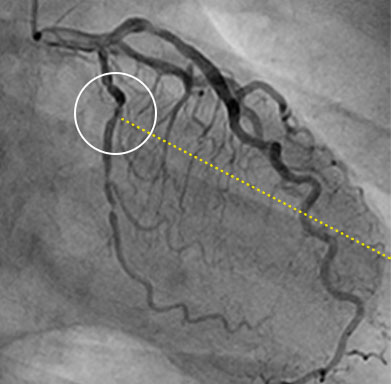

隠れた局所性病変により残存虚血が発生¹⁰

4名のうち1名の患者が、PCI後に残存虚血を抱えたままカテーテル検査室を後にします。その多くは隠れた局所性病変によるものです。¹⁰

iFR の値を血管造影図に直接マッピングできるため、血管のどの部分が虚血を起こしているのか、正確に見ることができます